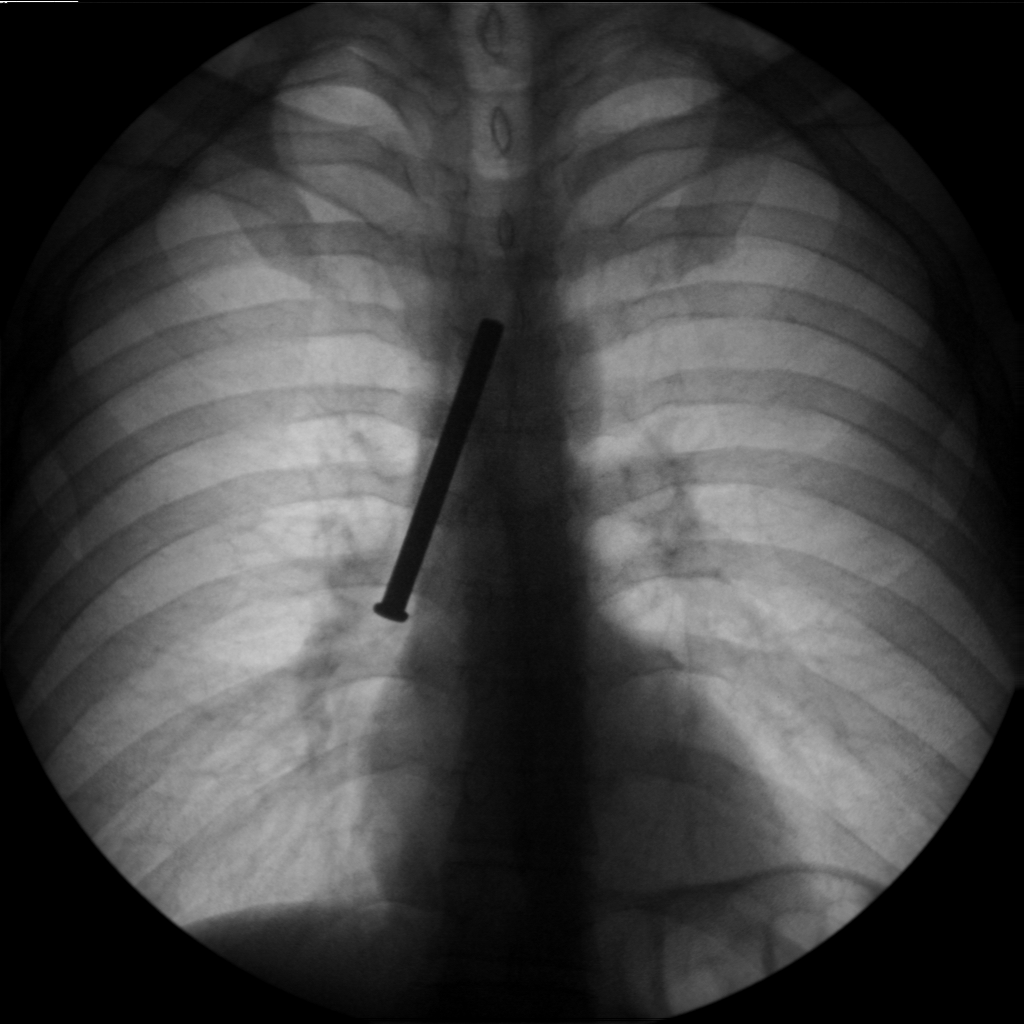

31 წლის პატიმარმა თვითდაზიანების მიზნით გადაყლაპა რამოდენიმე ნივთი, მათ შორის ერთი რკინის ნივთი გადასცდა, რის გამოც გაუძნელდა სუნთქვა, გაუჩნდა სტრიდორი, ძლიერი ტკივილი მარჯვენა გვერდში მოძრაობის დროს. საციცოცხლო ჩვენებით, ზოგადი გაუტკივარების პირობებში ჩატარდა რიგიდული ბრონქოსკოპია. გამოყენებული იყო ყველაზე დიდი ზომის ტუბუსი №13. ამოღების პროცესს ართულებდა უცხო სხეულის დიდი ზომა (სიგრძეში 10სმ). რამოდენიმე წარუმატებელი მცდელობის ბოლოს მოხერხდა უცხო სხეულის ექსტრაქცია. მანიპულაცია ჩატარდა გართულებების გარეშე.

- დიდი ზომის უცხო სხეული მარჯვენა მთ/ბ